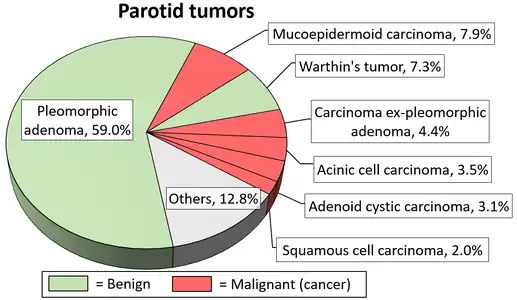

Little is known about the total incidence of salivary gland tumours as most benign tumours go unrecorded in national cancer registries.[3] The majority of salivary tumours are benign (65-70%).[4] Within the parotid gland 75 - 80% of tumours are benign. Around 50% of the tumours found in the submandibular glands are benign. Sublingual gland tumours are very rare but if present, they are most likely to be malignant.[4][19] Saku et al. in 1997 [20] and Venturi [21][22] in 2021, reported the causal role for ionizing radiation in salivary gland tumorigenesis, particularly for mucoepidermoid carcinoma.

Diagrams by Mikael Häggström - 1 2 Barnes L (23 December 2008). Surgical Pathology of the Head and Neck. Vol. 1 (3rd ed.). Taylor & Francis. p. 511. ISBN 978-0-8493-9023-4.